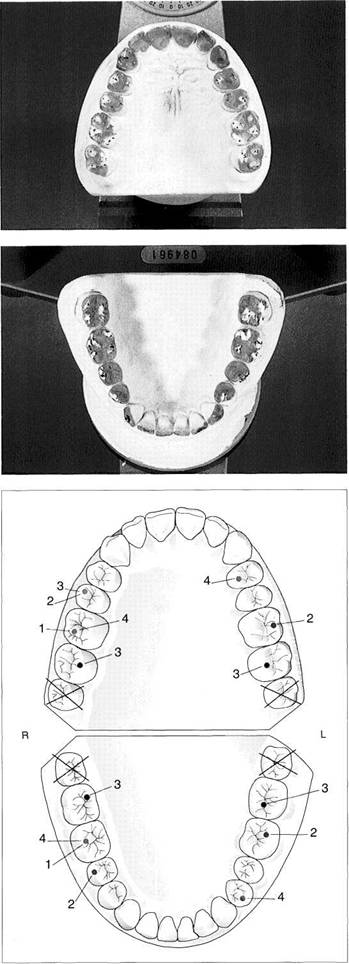

The Myomonitor procedure is counted among the semiac-tive techniques for the determination of centric jaw rela­tion. The Myomonitor, devised by Jankelson and Swain (1972), produces transcutaneous electrical nerve stimula­tion (TENS) which induces rhythmic contractions of the stimulated muscles. This in turn relaxes the muscles to achieve a mandibular rest position that is at least temporar­ily stable and relaxed. Electrical pulses, each lasting half a second and spaced 1.5 seconds apart, are conducted from two active preauricular electrodes to one indifferent elec­trode placed below the occipital bone.

On each side the Myomonitor delivers a maximum electri­cal potential of 65 V and, depending on the resistance of the skin, a maximum current of 25 mA. Through indirect stim­ulation of motor branches of the trigeminal and facial nerves, these pulses produce synchronous, mutually balanc­ing muscle contractions. After the Myomonitor has been used for 30-40 minutes the mandibular rest position can become stabilized to a great extent through fatigue and relaxation of the muscles of mastication. This newly defined rest position serves further as the starting point for registra-

The Myomonitor

The Myomonitor, shown here with its set of electrodes, electrode gel, and application syringe, can bring about relaxation of the muscles of expression and mastication through rhythmic transcutaneous electrical stimulation of the facial and masse­teric nerves.

Placement of the electrodes

The active electrodes are placed over the preauricular areas on both sides, and the indifferent electrode is centered on the back of the neck just below the hairline.

Right: Contact gel is applied to the skin with a syringe and spread even­ly by pressing on the electrode.

Cables connecting electrodes to the Myomonitor

The electrodes are connected to the Myomonitor through color-coded cables (green = right; black = left).

Regulation of the impulse intensity

The amplitude of the electrical im­pulse is adjusted for each individual patient with the head and upper body in the upright position and the teeth out of occlusion. A uni­form, rhythmic contraction of the elevator muscles should be visible.

Range of possible

mandibular rest positions (gray

areas)

Posselt diagram in the frontal plane. The rest position depends on a number of factors. Here the "my­ocentric" lies on the path of closure of the mandible approximately 3 mm superior to the rest position as determined through use of the Myomonitor.

Left: Sagittal view.

Position of maximum intercuspa-

tion

Retrusive contact position

Neutral rest position

Interocclusal registration

of the myocentric position

The Myomonitor serves here simply to introduce a relaxed and repro­ducible rest position from which the patient actively but gently clos­es into the registration material (here, Beauty-Pink-Wax refined with Aluwax).

Apart from this indirect procedure, a direct "myocentric" record can also be made by using the My­omonitor to "pulse" the teeth into a slow-setting registration material (e.g. Myoprint).